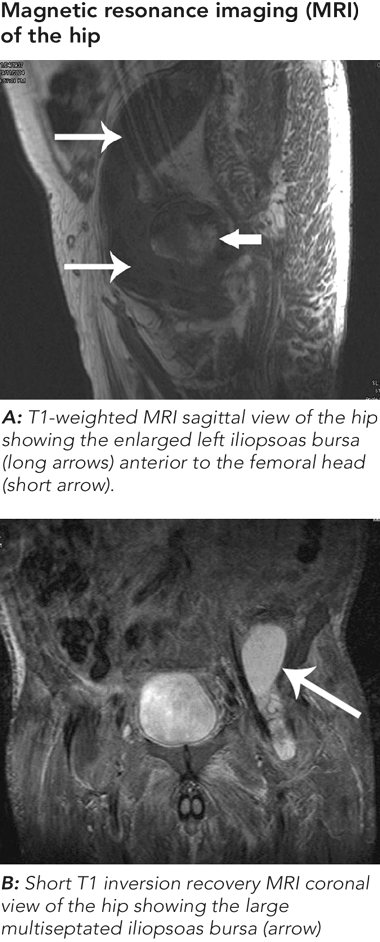

Magnetic resonance imaging (MRI) of the hip revealed a large iliopsoas collection with femoral head signal changes and flattening (Figures). An infective cause was suspected, so arthroscopic lavage of the left hip and computed tomography (CT)-guided aspiration of the iliopsoas collection were performed. The aspirate removed 50 mL of fluid containing mildly increased neutrophils, but showed no evidence of M. tuberculosis by microscopy, culture or PCR. Nuclear technetium-99 scintigraphy showed uptake only in the femoral head, suggestive of osteonecrosis, with a differential diagnosis of osteomyelitis. A subsequent CT-guided biopsy of the psoas collection wall did not show any evidence of tuberculosis by histology, culture or PCR.

The patient underwent a total hip replacement 8 months after his initial presentation with left hip pain. Histology of the hip revealed osteonecrosis of the femoral head, synovial inflammation from rheumatoid arthritis and no evidence of tuberculosis. The iliopsoas collection was thought to be due to a giant iliopsoas bursa that did not recur after aspiration.

Our patient had an enlarged iliopsoas bursa associated with osteonecrosis of the femoral head mimicking a tuberculous psoas abscess.